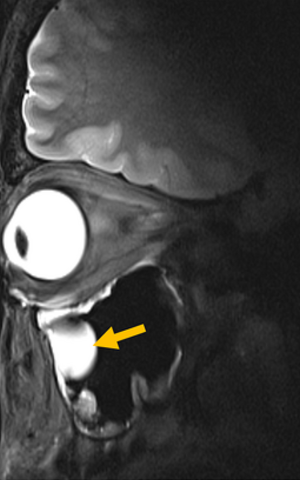

The research team addressed this bottleneck by integrating metamaterials directly into the MRI antenna. Metamaterials are engineered structures that interact with electromagnetic waves in ways not found in natural materials. The engineered RF antenna increases signal strength from targeted tissues, improves spatial resolution and image sharpness and enables faster data acquisition. Crucially, the antenna fits into existing MRI systems, avoiding the need for new infrastructure. The team validated the technology by imaging the eye and orbit region in a group of volunteers at 7.0 Tesla.

Our research demonstrates clear relevance for ophthalmological applications as it can facilitate anatomically detailed, high-spatial resolution MRI of the eye,” says Professor Oliver Stachs, a co-author of the paper at University Medicine Rostock. It offers the potential to open a window into the eye and into (patho)physiological processes that in the past have been largely inaccessible.”